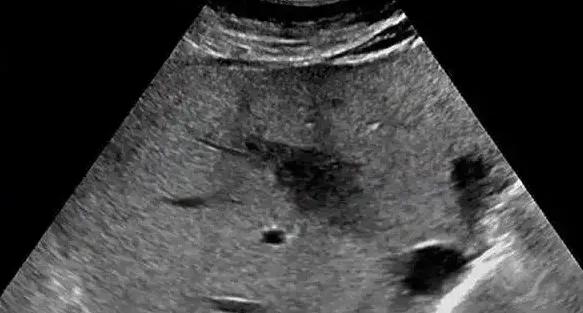

非均匀性脂肪肝是一种特殊的脂肪肝类型,其特点是脂肪在肝脏内的分布不均匀。与弥漫性脂肪肝不同,非均匀性脂肪肝在超声图像上表现为不规则的片状低回声或强回声区域,边界清晰,内部回声均匀。这种特殊的影像学表现常导致误诊,需要与肝肿瘤或肝血管瘤等疾病进行鉴别。